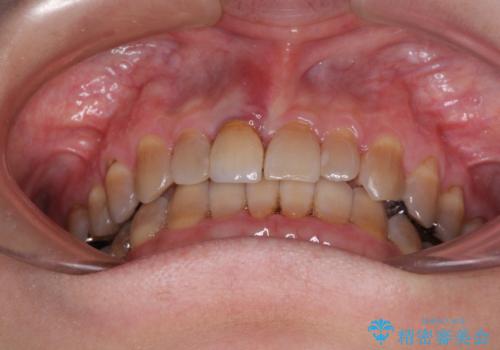

- 前歯のデコボコと、顎に負担のかかる歯並びを改善したいとのことで来院された患者様です。

うまく歯ぎしりができず、強く食いしばりをしてしまう咬み合わせであったため、奥歯に非常に負担がかかっていました。

インビザラインを用いて前歯のデコボコを改善するとともに、奥歯の咬み合わせを変えてスムーズに歯ぎしりできるように排列していくこととしました。

可能であれば上下正中を合わせ、左右の咬み合わせも改善したかったのですが、骨格的な左右差が大きかった上に、インビザラインでは限界があり、達成できませんでした。

それでも奥歯の負担を改善することができました。